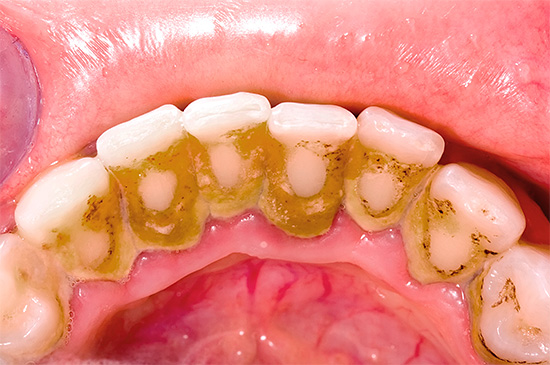

L'insorgenza o la possibilità di carie nel prossimo futuro può essere data anche dal tartaro. La foto mostra un esempio di tali depositi all'interno dei denti anteriori:

A causa del rinvio troppo lungo di una visita dal dentista, possono svilupparsi carie multiple, che è improbabile che aggiungano attrattiva a qualcuno:

Ecco un'altra foto che mostra la lesione simultanea della carie profonda di più denti contemporaneamente: